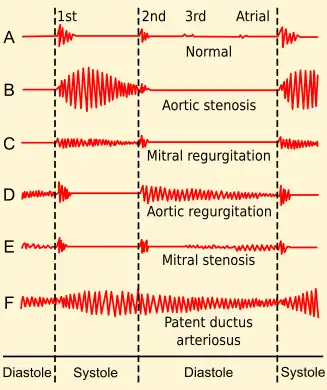

Findings on clinical examination depend on the severity and duration of MR. The mitral component of the first heart sound is usually soft and with a laterally displaced apex beat,[6] often with heave.[7] The first heart sound is followed by a high-pitched holosystolic murmur at the apex, radiating to the back or clavicular area.[6] Its duration is, as the name suggests, the whole of systole. The loudness of the murmur does not correlate well with the severity of regurgitation. It may be followed by a loud, palpable P2,[6] heard best when lying on the left side.[7] A third heart sound is commonly heard.[6]

Patients with mitral valve prolapse may have a holosystolic murmur or often a mid-to-late systolic click and a late systolic murmur. Cases with a late systolic regurgitant murmur may still be associated with significant hemodynamic consequences.[8]

There are many diagnostic tests that have abnormal results in the presence of MR. These tests suggest the diagnosis of MR and may indicate to the physician that further testing is warranted. For instance, the electrocardiogram (ECG) in long-standing MR may show evidence of left atrial enlargement and left ventricular dilatation. Atrial fibrillation may also be noted on the ECG in individuals with chronic mitral regurgitation. The ECG may not show any of these findings in the setting of acute MR.

Electrocardiography

P mitrale is a broad, bifid notched P wave in several or many leads with a prominent late negative component to the P wave in lead V1, and may be seen in MR, but also in mitral stenosis, and, potentially, any cause of overload of the left atrium.[18]